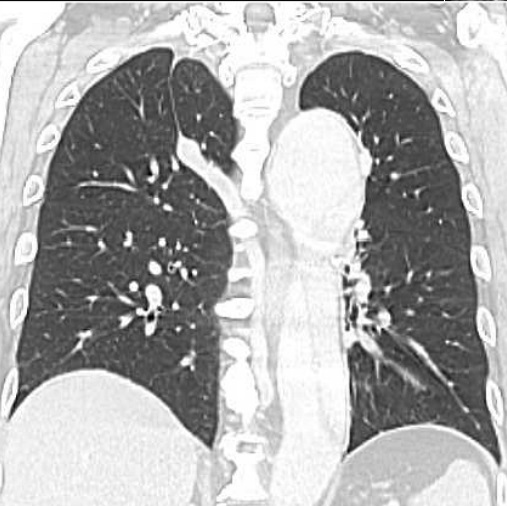

Image radiologique IRM

d'une pleuresie à moyen abondance à inferieur du

poumon droit en aspect IRM à hypointense , non

systematise, homogene situe au sinus

costo-diapragmatique latertal du poumon droit Image

IRM en coupe coronal ponderee sur T1 . |

Même cas en coupe IRM à

ponderee sur T2 . Aspect radiologique est de image

nonsystematise , homogene très hypersignal du

contenue liquidien dans espace pleurale |